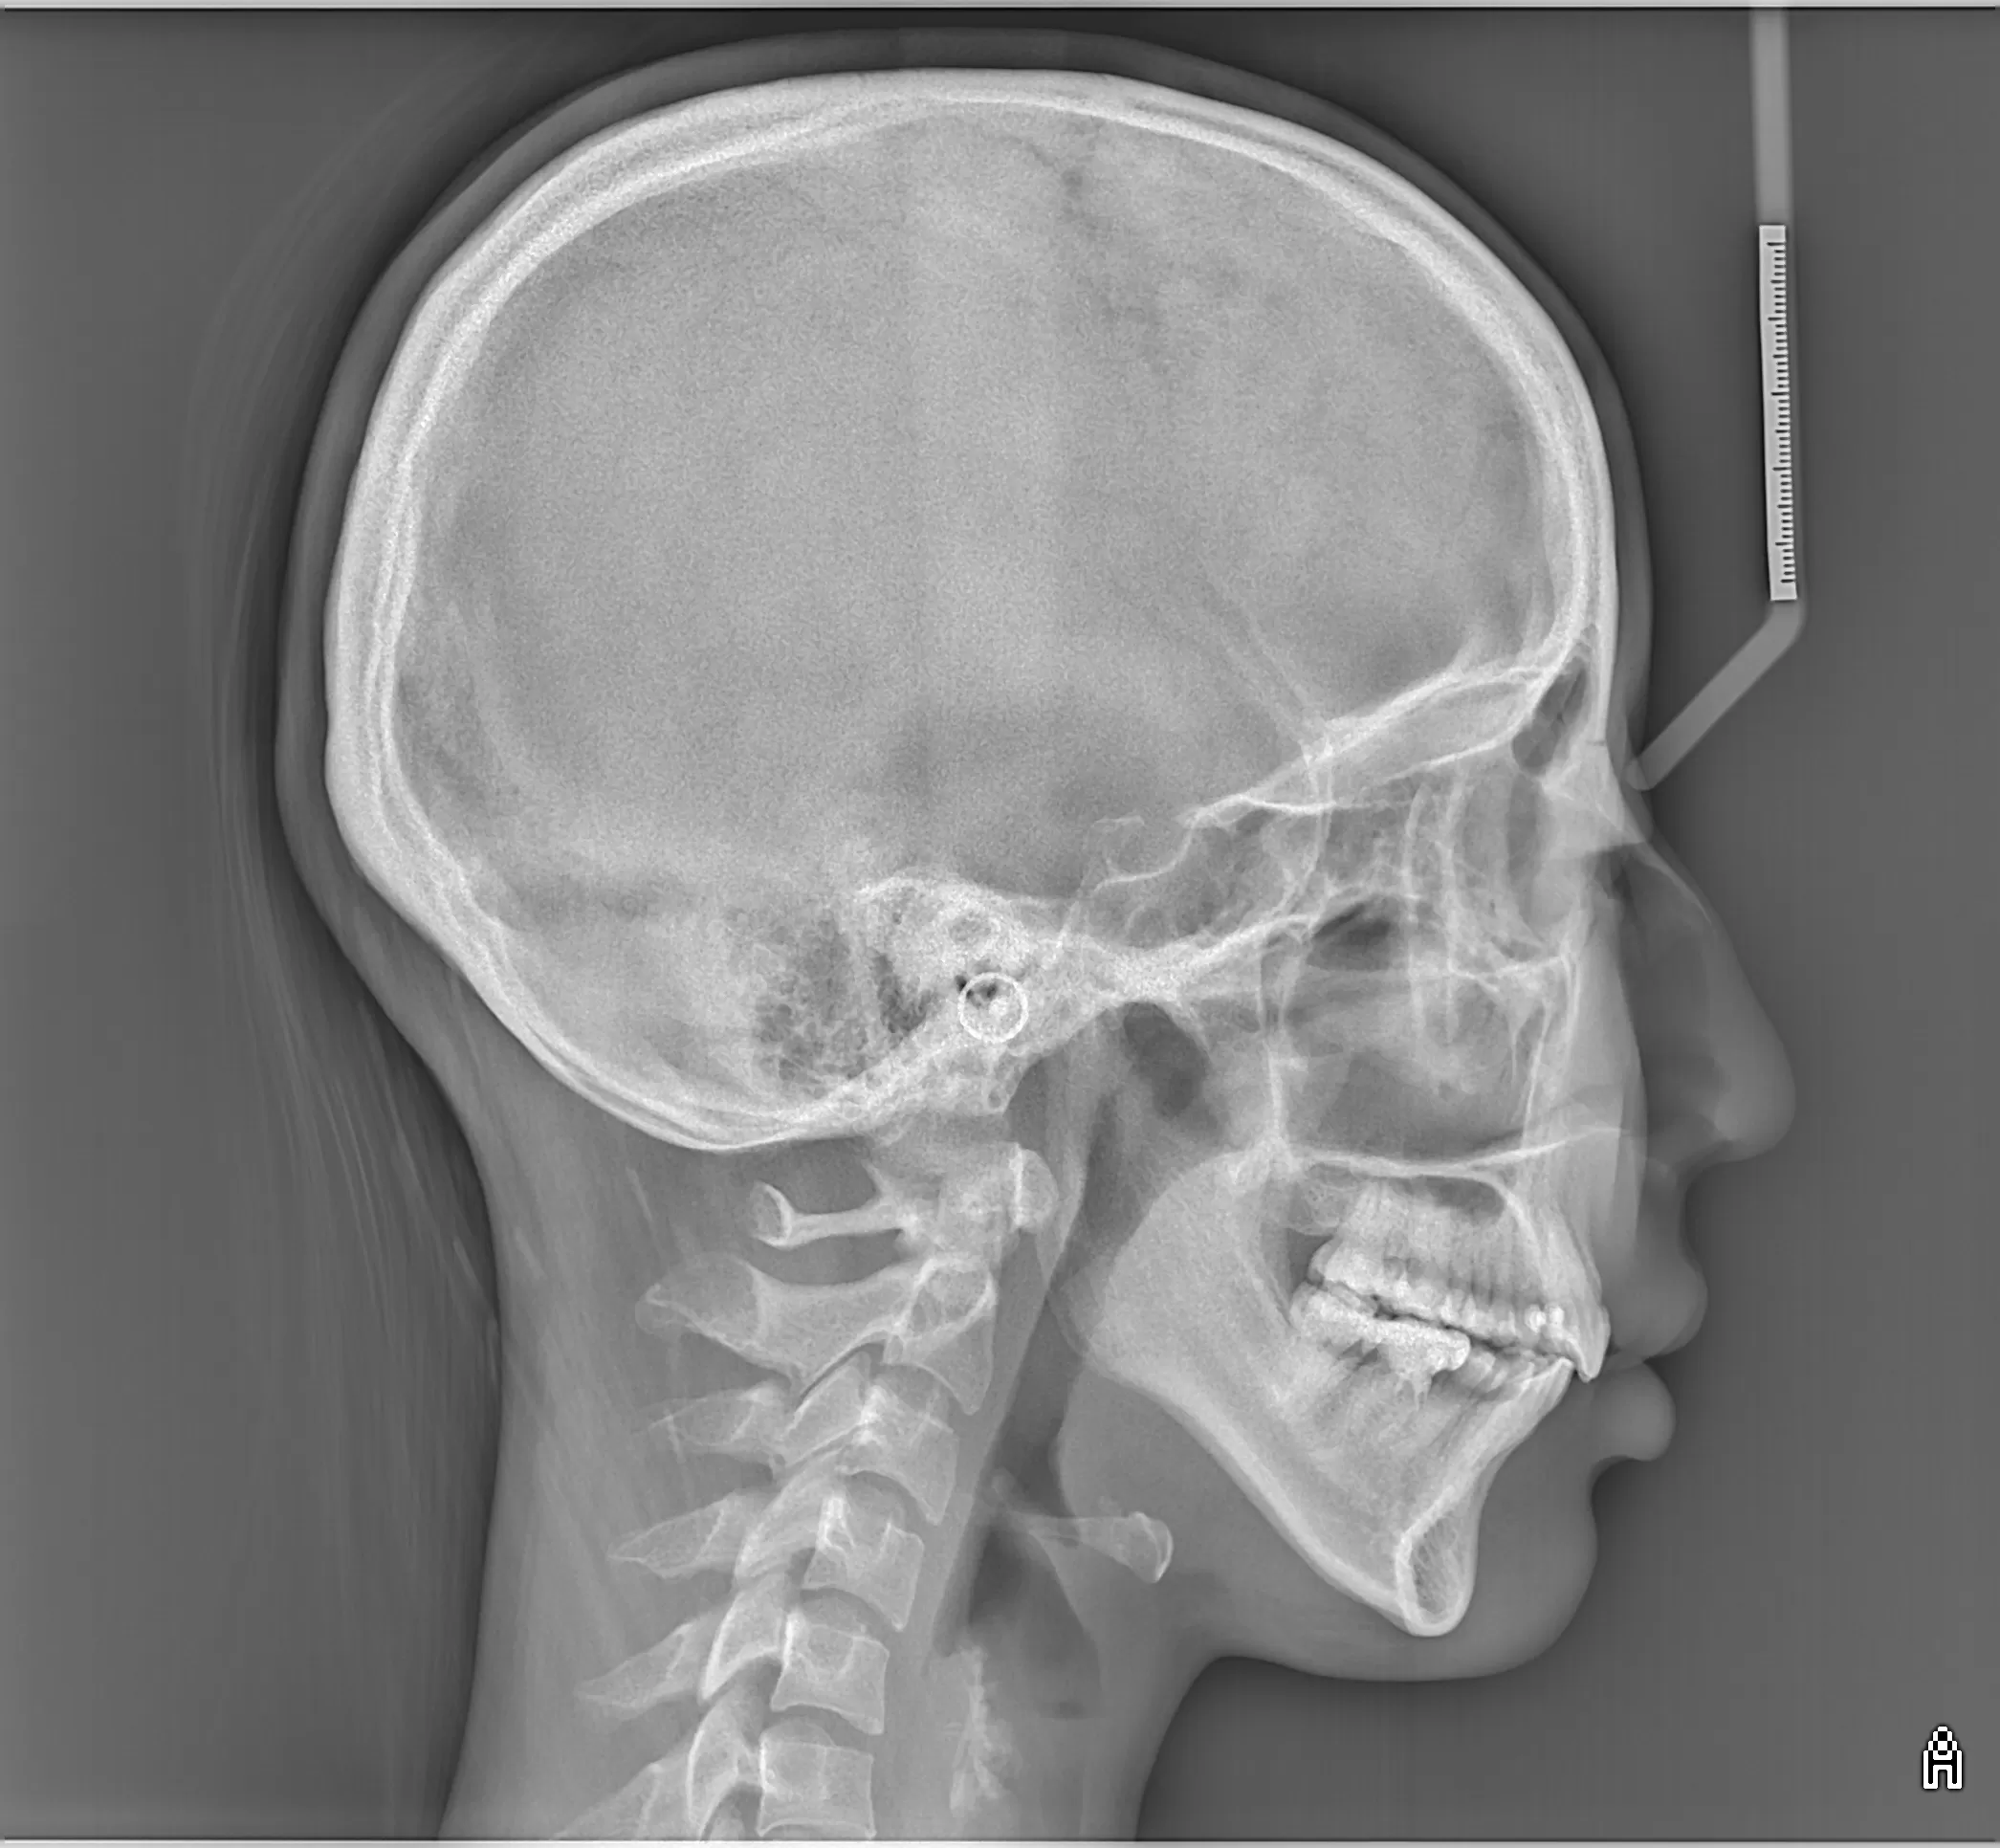

セファロで骨格を確認する。

上の歯が出てるのか、下の歯が引っ込んでいるのか?

それぞれ違うのです。